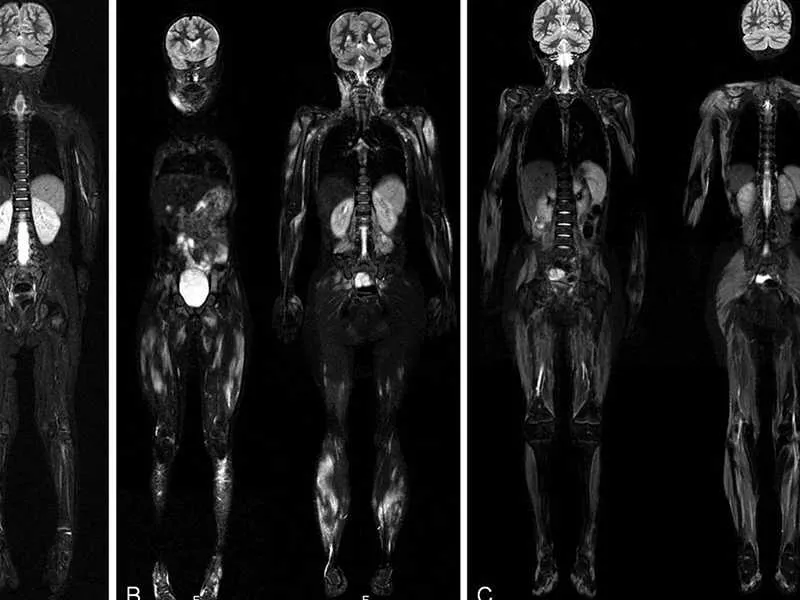

Tüm vücut MR, manyetik rezonans görüntüleme teknolojisi kullanılarak vücudun tamamının ayrıntılı bir şekilde taranmasıdır. Radyasyon içermeyen bu yöntem, manyetik alan ve radyo dalgaları yardımıyla organların ve dokuların yapısını detaylı bir şekilde gösterir. Doktorlar, bu görüntüleri kullanarak hastalıkları teşhis eder ve tedavi planlarını oluşturur.

Tüm vücut MR, özel bir cihazda yatay pozisyonda yatarak gerçekleştirilir. Hasta, cihazın içinde hareketsiz kalır ve manyetik alan ile radyo dalgaları yardımıyla görüntüler elde edilir.